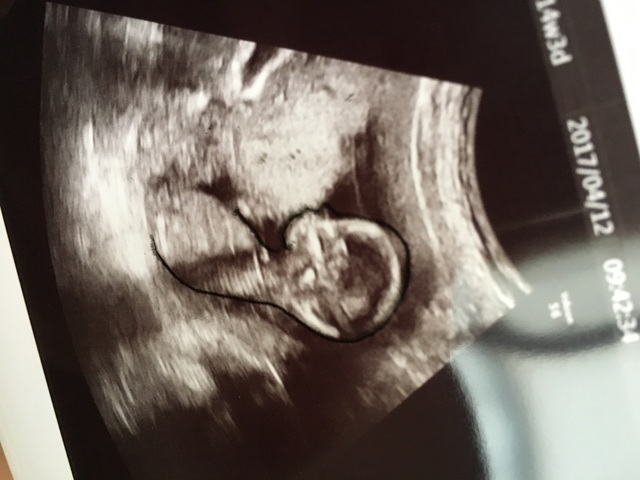

14週0日(14w0d・性別不明)|natsuki. さん(24歳)

エコー写真撮影時のエピソード:

3週間ぶりの検診で小心者の私のドキドキ、不安とは裏腹に前回の検診より成長しており一安心。初めて心音も聞かせてもらって、より一層実感が増しました。

内診中も凄い元気に飛び跳ねててかわいかったな。次の検診は4週間後なので今から楽しみ。